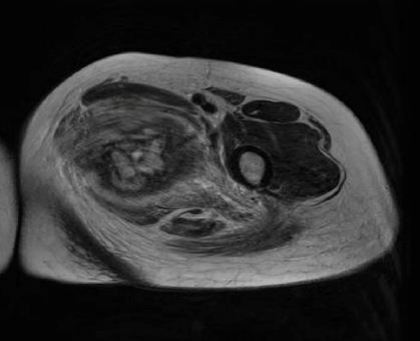

Magnetic resonance imaging (MRI) revealed a 4.7x7.2x9 cm irregular soft tissue mass in the left medial proximal thigh involving the adductor magnus muscle. The mass demonstrated intermediate and heterogeneous T2 signal intensity with an irregular peripheral T2 dark signal rim and intermediate T1 signal intensity. Additionally, the MRI showed extensive surrounding muscle and subcutaneous edema with a branch of the deep femoral artery coursing through the mass. Gadolinium-enhanced images revealed multilocular cystic areas surrounded by intense heterogeneous enhancement of the solid components. The mass demonstrated features concerning for malignancy [Figure 1, 2, 3, 4]. A fluorodeoxyglucose (F-18 FDG) PET scan demonstrated mildly hypermetabolic lymph nodes in the left inguinal region (suspected reactive) and a few small inflammatory nodules without FDG uptake in both lungs, but no evidence of distant metastasis [Figure 5].

FIGURE 1: Axial T1-weighted MR image Intermediate T1 signal intensity of the medial thigh mass involving the adductor magnus muscle

FIGURE 3: Axial T2-weighted MR image  Mass appearing with intermediate and heterogeneous signals